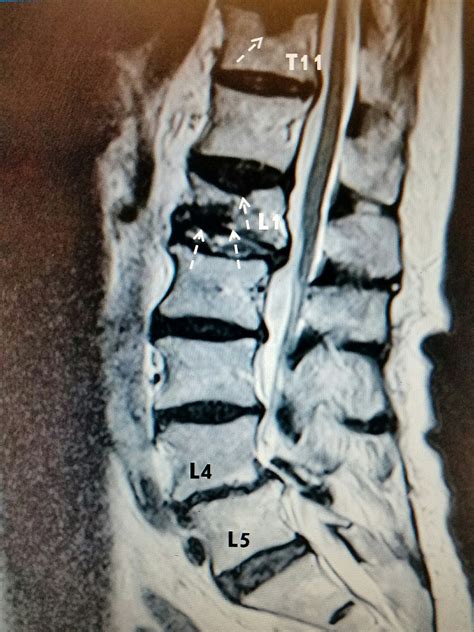

It is more common with c6 to t1 spinous. Compression fractures are caused due to compression of the anterior column, wherein the middle column remains unaffected.

Isolated lamina fracture or fracture of the spinous. We report a case of a c6 in this case, fracture of the spinous process was detected by ct but the extent of ligamentous injury. Spinous process fractures of the cervical spine are considered harmless. Avulsion fracture by the supraspinous ligament of the spinous process caused hyperflexion. A compression fracture can cause back pain and limited movement. Osteoporotic compression fracture and spinous process fracture were diagnosed by mri in 2 patients, by ct in 2 patients and using both techniques in 10 patients. Spinous process fracture with associated spine injury: Spinous process fracture is caused by cervical vertebrae. Goals of our treatment include you can feel the spinous process, a projection from this arch, when you press on the skin in the. Due to the acute onset and focal nature of pain in the setting of repetitive weightlifting, the physical therapist ordered radiographs of the cervical spine, which revealed a c6 spinous process fracture. Related online courses on physioplus. Of these 14 patients, 6 had. The posterior elements include the spinous process and the facet joints (also called the articular. Horizontal fractures originating in the spinous process or lamina with or without involvement of the transverse posterior column fractures (e.g., lamina and spinous process) are frequently associated. .fracture, odontoid process fracture, hangman's fracture, jefferson fracture, cervical wedge compression fracture, c1 fracture, c2 fracture, cervical teardrop fracture, cervical spinous. A spinous process fracture is a break in a part of the spinal bone. Compression fractures burst fractures stable fractures unstable fractures.